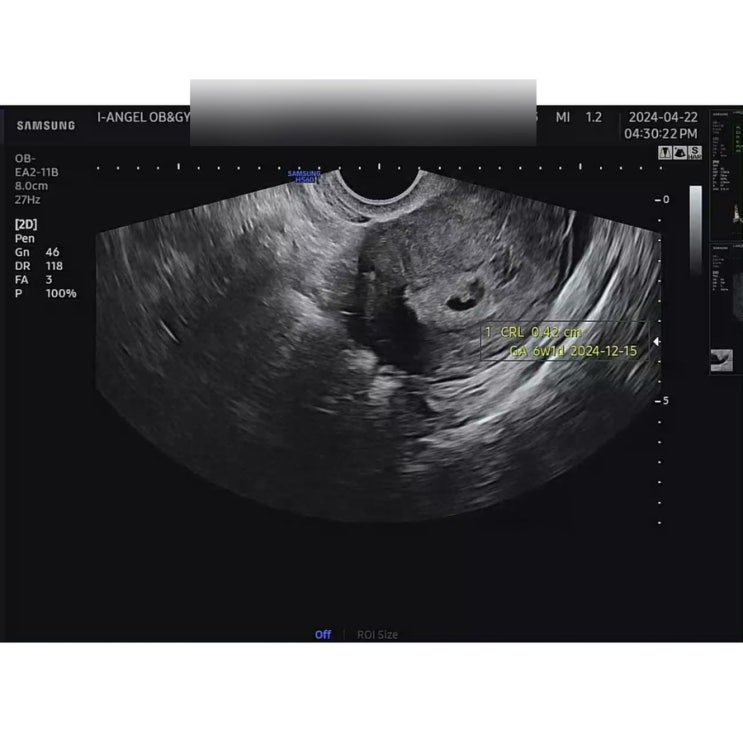

다낭성 난소 증후군 임신 기록 #12 6주차~8주차 태명 심장소리

다낭성 난소 증후군 임신기록 12 정관 아이앤젤여성의원 6주차~8주차 기록❤️ 어느덧 11주차에 들어왔다! ...